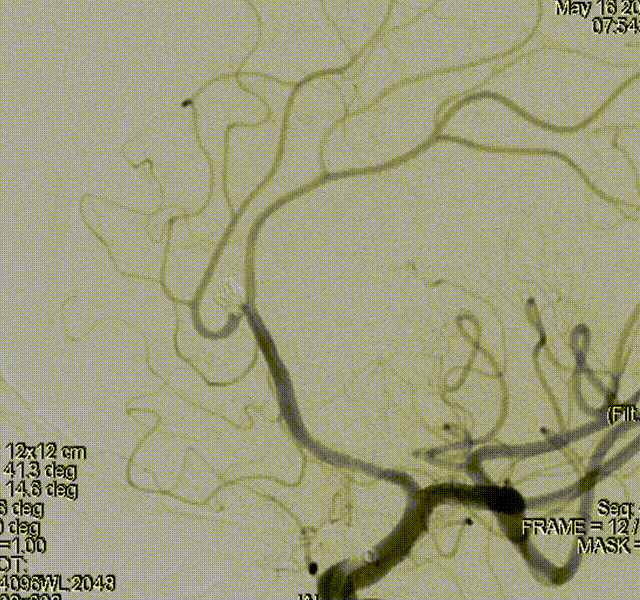

左侧大脑中动脉动脉瘤

术前影像

栓塞过程

先通过微导管填塞成篮圈,输送支架到左侧大脑中动脉下干并释放,使支架覆盖动脉瘤开口。依次填入Jasper®SS弹簧圈多枚。

术后即刻影像

术者体会

Experience

左侧大脑中动脉分叉部动脉瘤呈分叶状,有子瘤,破裂风险大,累及大脑中动脉上下干,且动脉瘤形态不规则,需分区填塞。填塞使用的Jasper®SS弹簧圈圈体柔软,在瘤内钻缝能力强,能够很好地达到填塞效果,柔软性能强,基本不踢管,电解脱快速顺利,增加了手术的安全性及成功率。